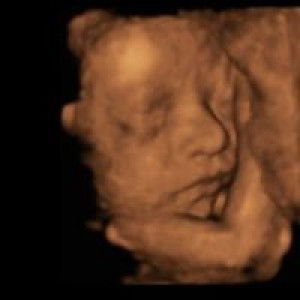

Birthclub: Disyembre 2023

okay lang ba naka dapa habang nadede si baby dito kasi sya nakalma at natigil sa pagiyak

#firsttimemom #2monthsoldBabyboy